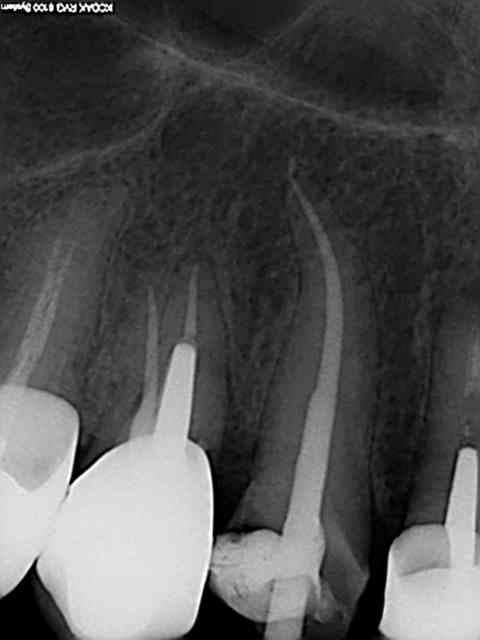

R29 uvltlt - Eugenol

R49 enunsh - Eugenol

R22 vkd0tr - Eugenol

R23 pmkimv - Eugenol

R26 gr1kkt - Eugenol

R34 w9wpow - Eugenol